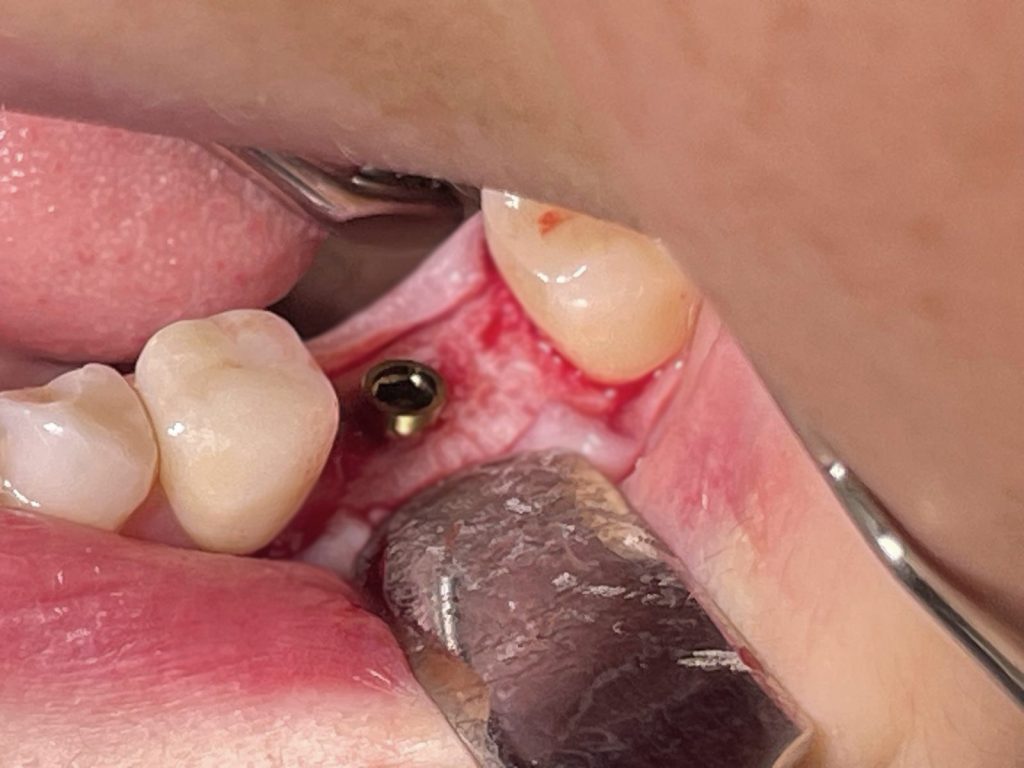

In questo caso specifico, con l’impianto PRAMA di Sweden&Martina è possibile gestire il posizionamento in senso apico-coronale per poter tenere la connessione impianto/abutment sovracrestale; in questo modo è possibile tenere l’eventuale infiltrato batterico lontano dal tessuto osseo.

Ne deriva un miglior risultato nel tempo e si riduce il rischio di perimplantiti.